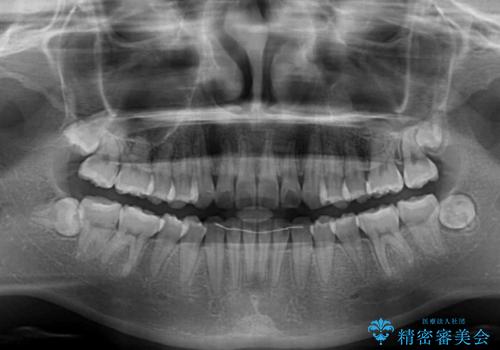

しっかりと装着時間を守ってくださったので、予定通り1年強で治療を終えることができました。